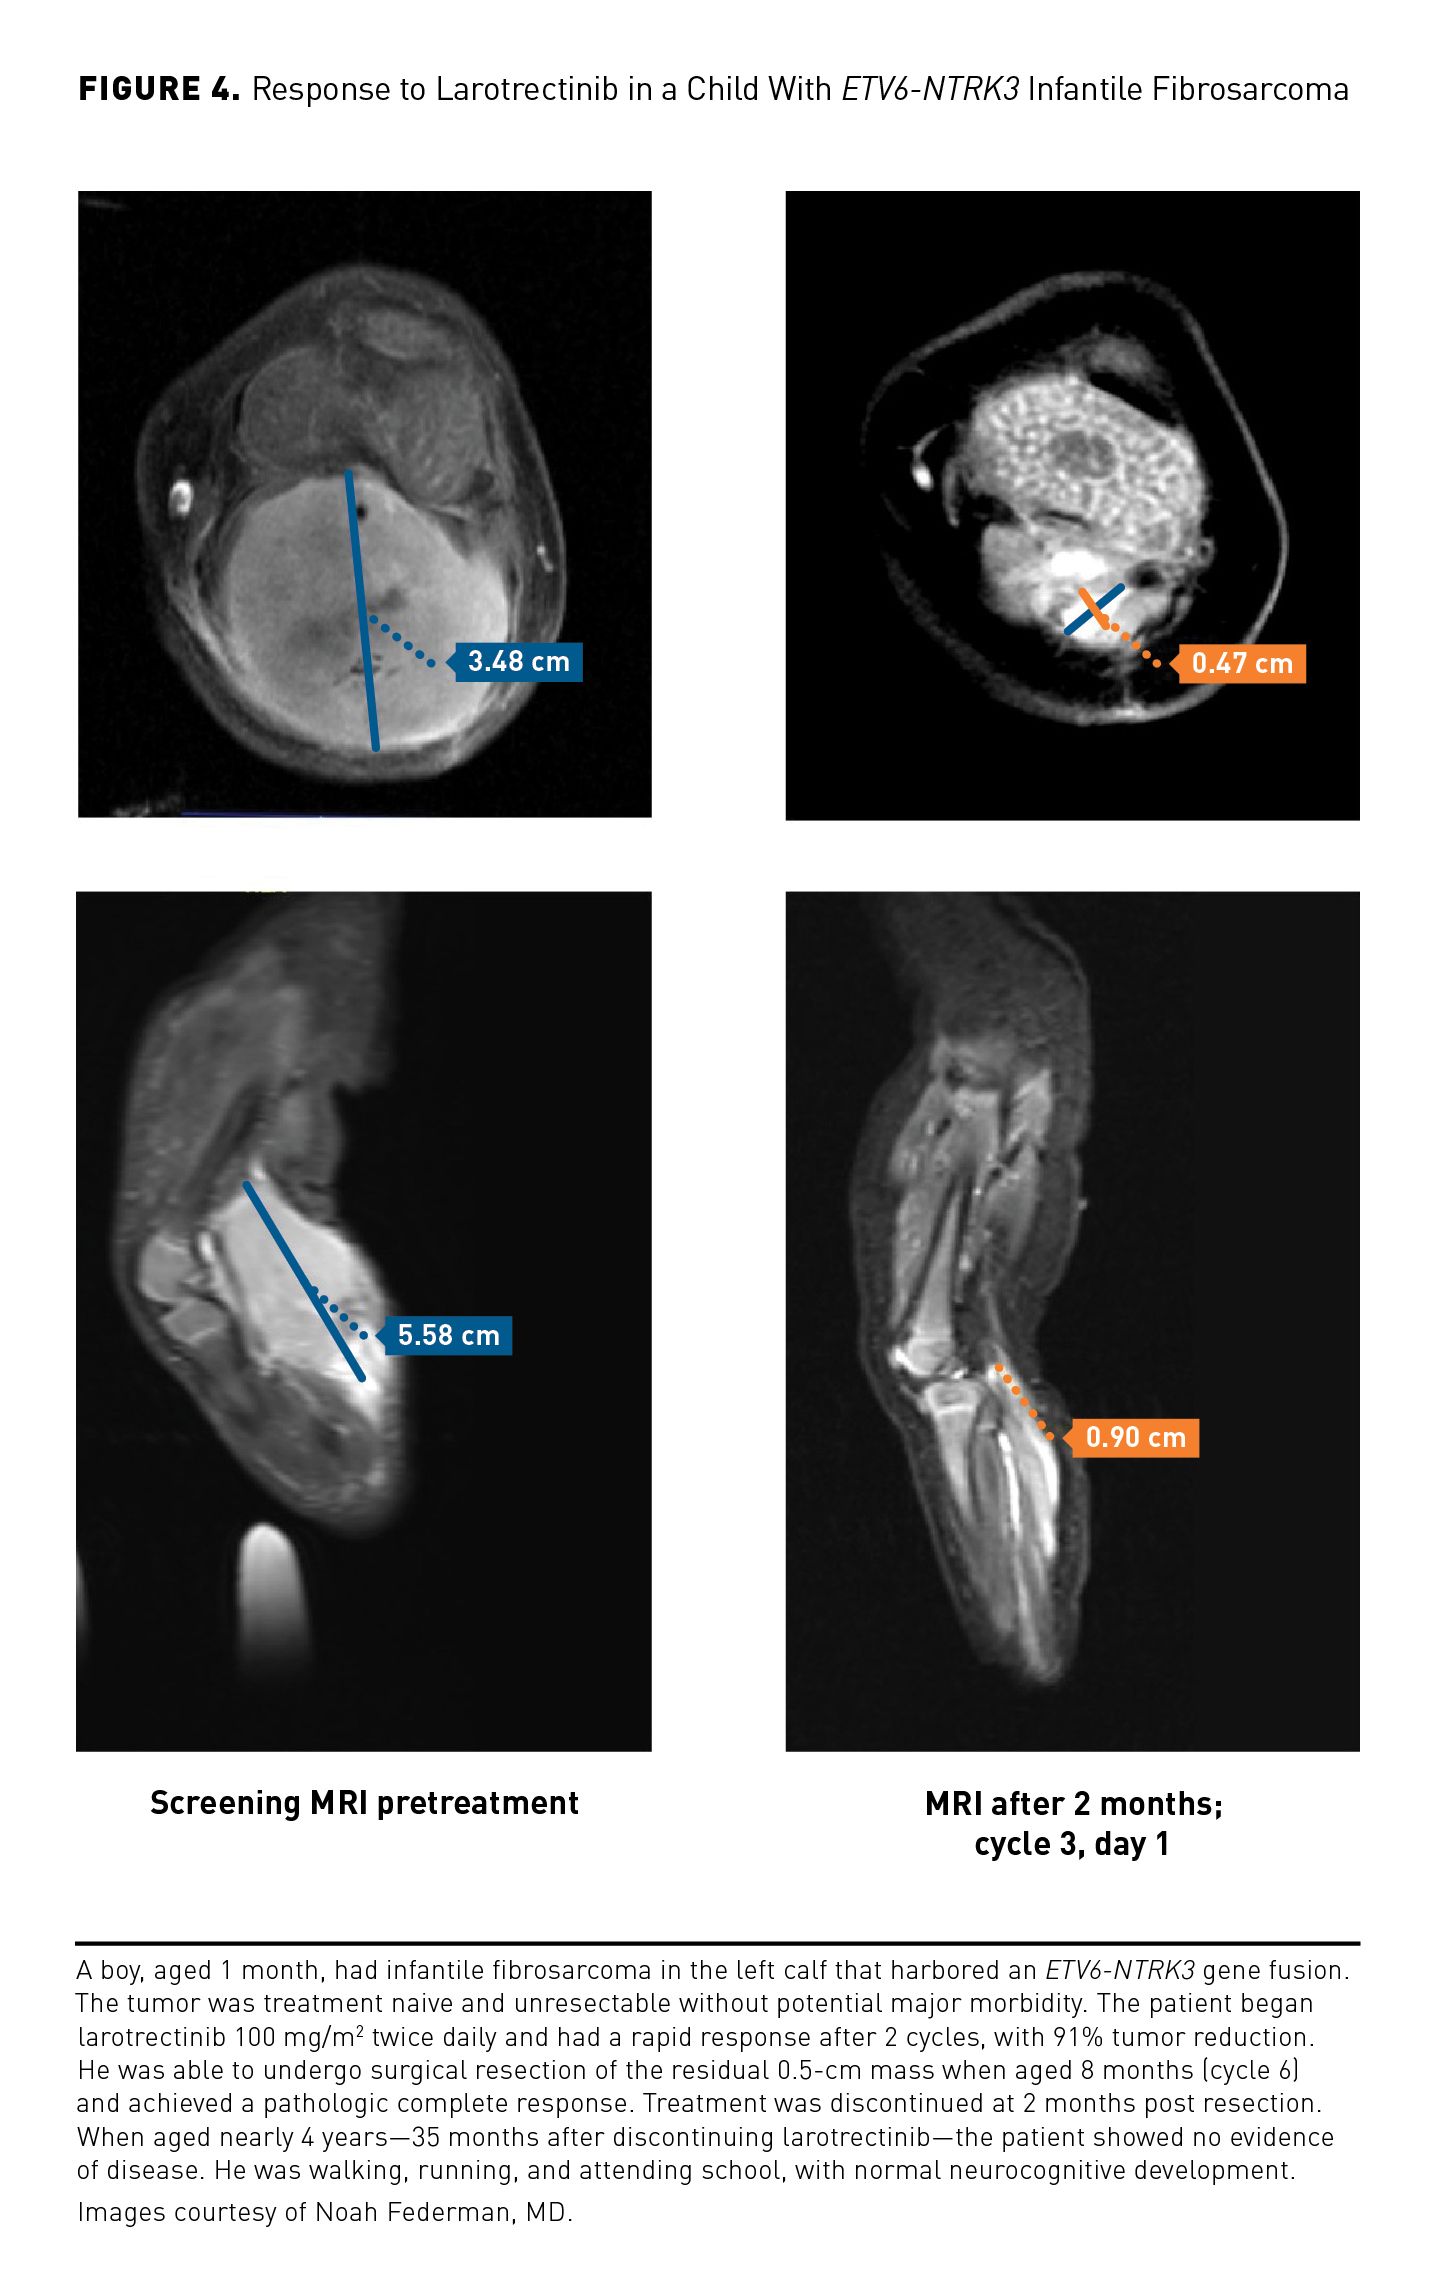

The larotrectinib clinical development program is unique, as it encompassed patients across the age spectrum, including children aged as young as 1 month, and with a wide range of tumor types. The efficacy and safety of larotrectinib was evaluated in 3 phase 1/2 clinical studies in adults and children with TRK fusion cancer, who received doses of 100 mg (adults) or 100 mg/m2 (children) twice daily; these were an adult phase 1 study (NCT02122913) and the SCOUT (NCT02637687) and NAVIGATE (NCT02576431) trials.30,34 The objective response rate (ORR) from a pooled analysis of these 3 studies (N=55) was 75% (95% CI, 61%-85%) per independent review and 80% (95% CI, 67%-90%) per investigator assessment, with responses seen regardless of age, tumor type, specific NTRK gene, or fusion partner. At 1 year, 71% of the responses were ongoing and 55% of patients were progression free. The majority of AEs were grade 1/2, and there were no treatment discontinuations due to AEs.30 In an expanded data set of 218 patients with TRK fusion cancer, the investigator-assessed ORR was 75% (95% CI, 68%-81%)(Table 3),28,29 and median duration of response (DOR) was 49.3 months (95% CI, 27.3 to not estimable [NE]).35 Median progression-free survival (PFS) was 35.4 months (95% CI, 23.4-55.7), and median overall survival (OS) was not reached.35 Responses were seen with larotrectinib across the spectrum of tumor types included in the study (Figure 2A).35 The clinical benefits of larotrectinib are illustrated in Figure 336 and Figure 4. Treatment-related AEs (TRAEs) observed in larotrectinib clinical trials were predominantly of grade 1/2; grade 3/4 TRAEs were reported in 18% of patients, the most common of which were decreased neutrophil count (7%), increased alanine aminotransferase (3%), and increased aspartate aminotransferase (2%).